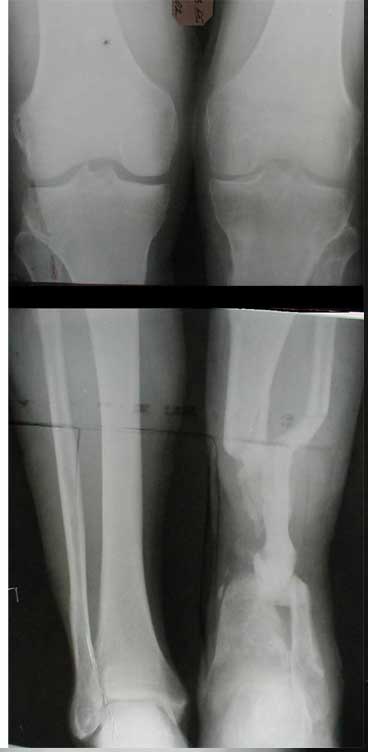

Dorogie kollegy,Have a nice day,Ja bi hotil obsuzdat' s Vami dvuh bolnih, kotorie postupili segodnjia ko mene. Pervy iz nih (OI) bolnoi s otkritoi tiazeloi mehanicheskoi travmoi Rt. leg segment v rezultate DTP, ot chego on imeet sledueshie povrezdenjia:- Otkrity perelom kostei pravoi goleny v srednei i niznoi ee trety s poteriem okolo 10 cm. kostnogo veshestva ot bolshebersovoi kosty, - Povrezdenjia a.tibialis post. s massivnim povrezdeniem zadneoi gruppy musculs goleny,- Malobersovjia kost' imeet segmentarny perelom, ee nizny fragment (kak Vi videte na foto) vistupaet na kozy okolo VNUTRENNOI Lodizky! - Traumaticheski Shock 2-3Drugih povrezdenjia net.

Nemedlenno bolnoi bil' intubirovan i provedeny vse protivoshokovie procedury, pravjia golen' bila pomeshenjia na apparat' Storm, dla reduksii kostei posle ee fiksasii k apparatu s pomoshio 2 spitsy 3mm D. Provedena Repozitsia pereloma i fiksirovana STORMOM vremenno, za tem sosudisty hirurg vypolnil 2 obhodnih anastomosa for a. Tibilis posterior, bili udaleny bolshie chasty iz musculov zadnoi gruppy goleny v predelah "vozmozno vedemih" zdorovoi tkany, oblast' pereloma promita by N. sol. 0.9% - 12 L. Zatem byla proizvedena okonchatenjia reduksia pereloma posle umerennoi traksii goleny na apparate, i fiksasiya pereloma s pomoshio apparata vneshnei fiksasii. Tak, Kakie soobrazanjia po dalneshemu vvdenjia bolnogo? On poluchaet antibiotiky i bolshie dozy LMH (Clexane 80 X 2) i vse ostalnoe......

1. Хотелось бы посмотреть рентгенограммы после фиксации в

аппарате. Ну и основной вопрос - жизнеспособна ли стопа.